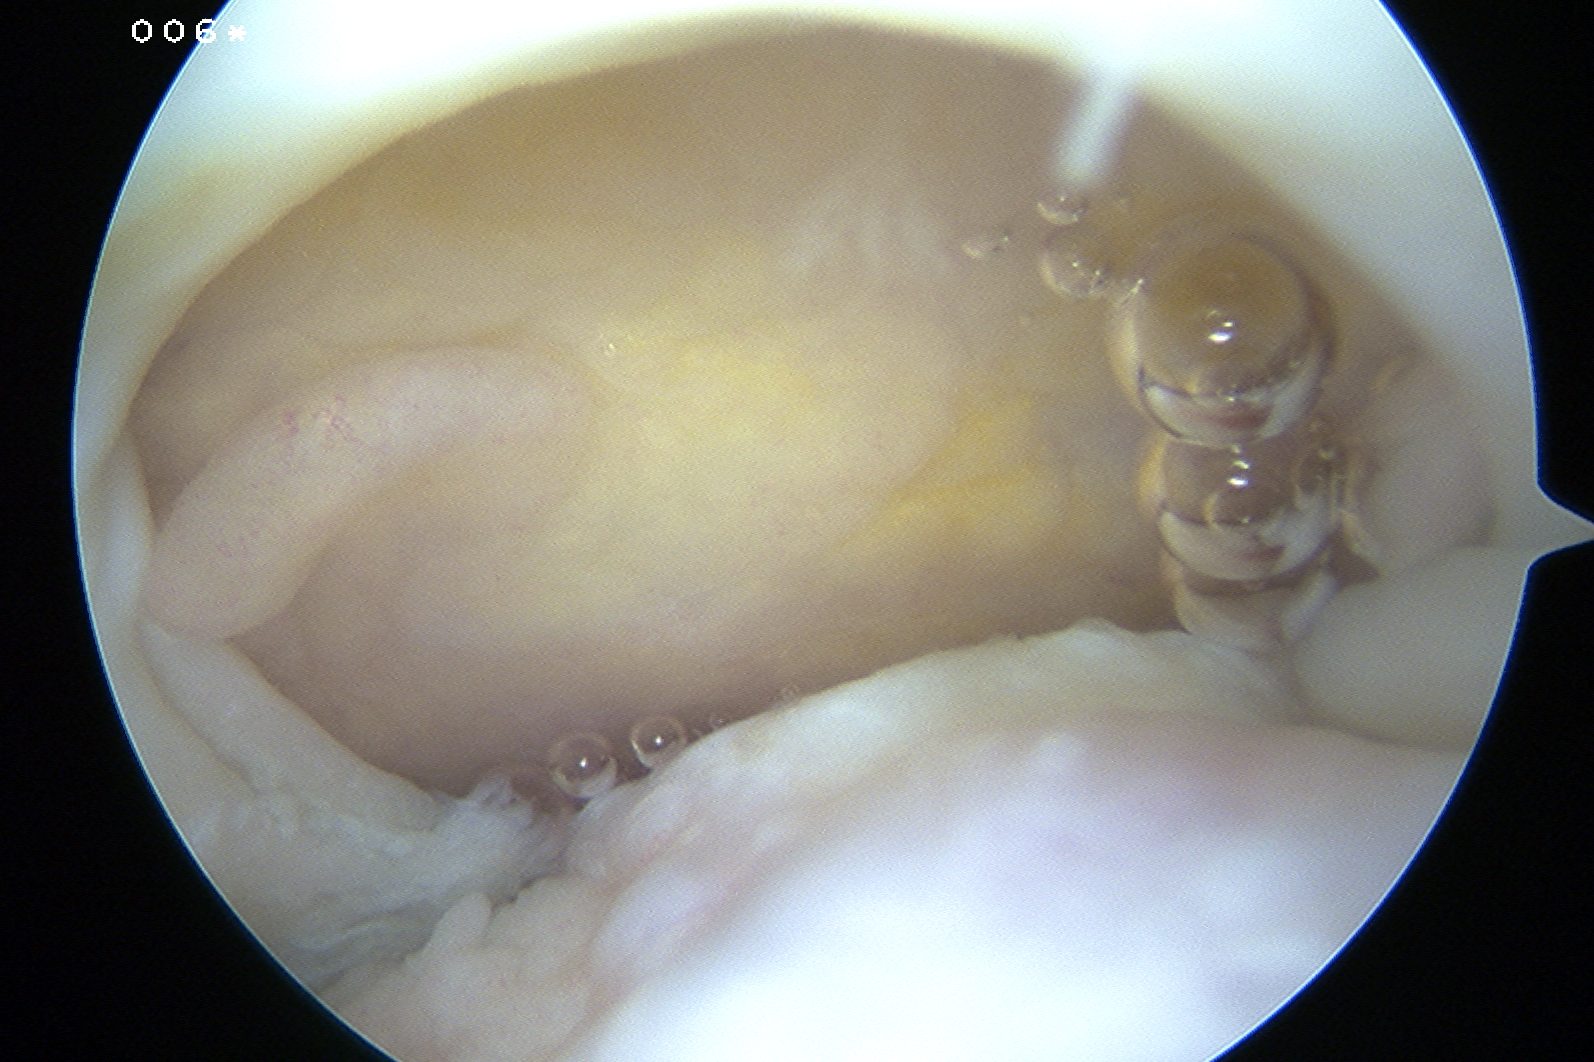

Glenohumeral joint

- inspect subscapularis

- evaluate SLAP / LHB tendinosis - tenotomy / tenodesis

Assess tear

- large tears may need releases

- consider margin convergence sutures for large U shaped tears

Margin convergence sutures

Medial row anchors

- inserted through additional stab incision for suture management

- just medial to articular cartilage

Pass sutures through medial cuff tendon

- camera posterior

- suture passer via lateral portal

- retrieve sutures through anterior portal

- repeat

- tie medial row

Double row / suture bridge

- use medial row sutures

- secure in knotless lateral row anchors